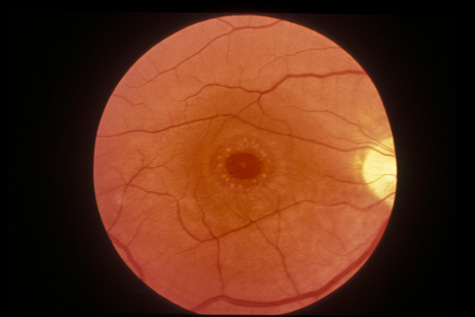

or internal limiting membrane removal. Ophthalmology 111:142, 2004 74. Yamashita T, Uemara A, Uchino E, et al: Spontaneous closure of traumatic macular hole. Am J Ophthalmol 133:230, 2002 75. Johnson R, McDonald HR, Lewis H, et al: Traumatic macular hole: observations, pathogenesis, and results of vitrectomy

surgery. Ophthalmology 108:853, 2001 76. Weidenthal DT, Schepens CL: Peripheral fundus changes associated with ocular contusion. Am J Ophthalmol 62:465, 1966 77. Jungschaffer OH: Arrowhead tear in the macula. Arch Ophthalmol 86:19, 1972 78. Hagler WS, North AW: Retinal dialysis and retinal detachment. Arch Ophthalmol 79:376, 1968 79. Ross WH: Retinal dialysis: lack of evidence for a genetic cause. Can J Ophthalmol 26:309, 1991 80. Smiddy WE, Green WR: Retinal dialysis, pathology and pathogenesis. Retina 2:94, 1982 81. Tasman W: Peripheral retinal change following blunt trauma. Trans Am Ophthalmol Soc 70:190, 1972 82. Sellors PJ, Mooney D: Fundus changes after traumatic hyphema. Br J Ophthalmol 57:600, 1973 83. Doden W, Stark N: Retina and vitreous findings after serious indirect trauma. Klin Monatsbl Augenheilkd 164:32, 1974 84. Cox MS, Schepens CL: Retinal detachment due to ocular contusion. Arch Ophthalmol 76:678, 1966 85. Winslow RL, Tasman W: Juvenile rhegmatogenous retinal detachment. Trans Am Acad Ophthalmol Otolaryngol 85:607, 1978 86. Raman SV, Desai UR, Andrerson S, et al: Visual prognosis in patients with traumatic choroidal rupture. Can J Ophthalmol 39:260, 2004 87. Fuller B, Gitter K: Truamatic choroidal rupture with late serous detachment of the macula. Arch Ophthalmol 89:354, 1973 88. Hilton GF: Late serosanguinous detachment of the macula after traumatic choroidal